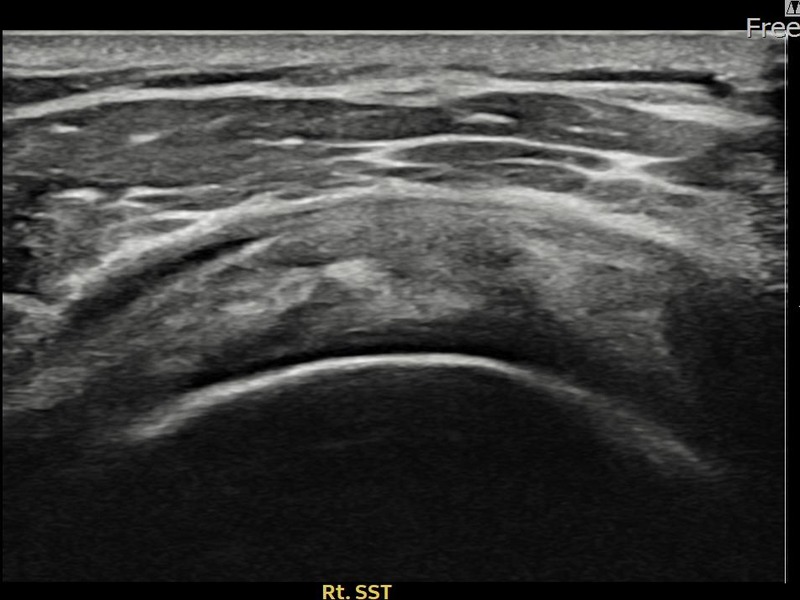

유ㅇㅇ님 · 우측 견갑하근건 관절면측 부분파열

우측 어깨 전방 통증과 팔 내회전 제한으로 내원하셨습니다. 초음파 검사에서 견갑하근건 관절면측 부분파열이 확인되었으며, 어깨인대 축소봉합술 후 힘줄 구조적 안정화가 이루어졌습니다.